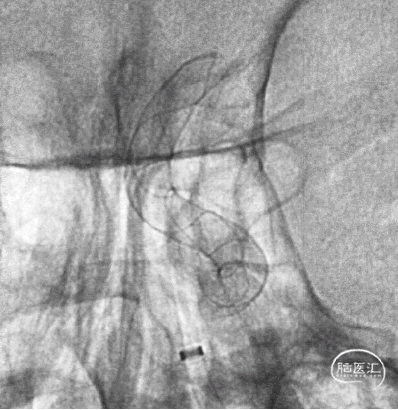

经桡动脉入路左侧颈内动脉通路建立

Fastrack微导管到位

TB Plus 4/35

3、释放TB Plus过程中,头端铆钉效果满意,释放过程顺滑。

4、通过微导丝按摩,可以使TB Plus贴壁效果更加。

5、FD植入后,动脉瘤明显造影剂瘀滞,效果显著。